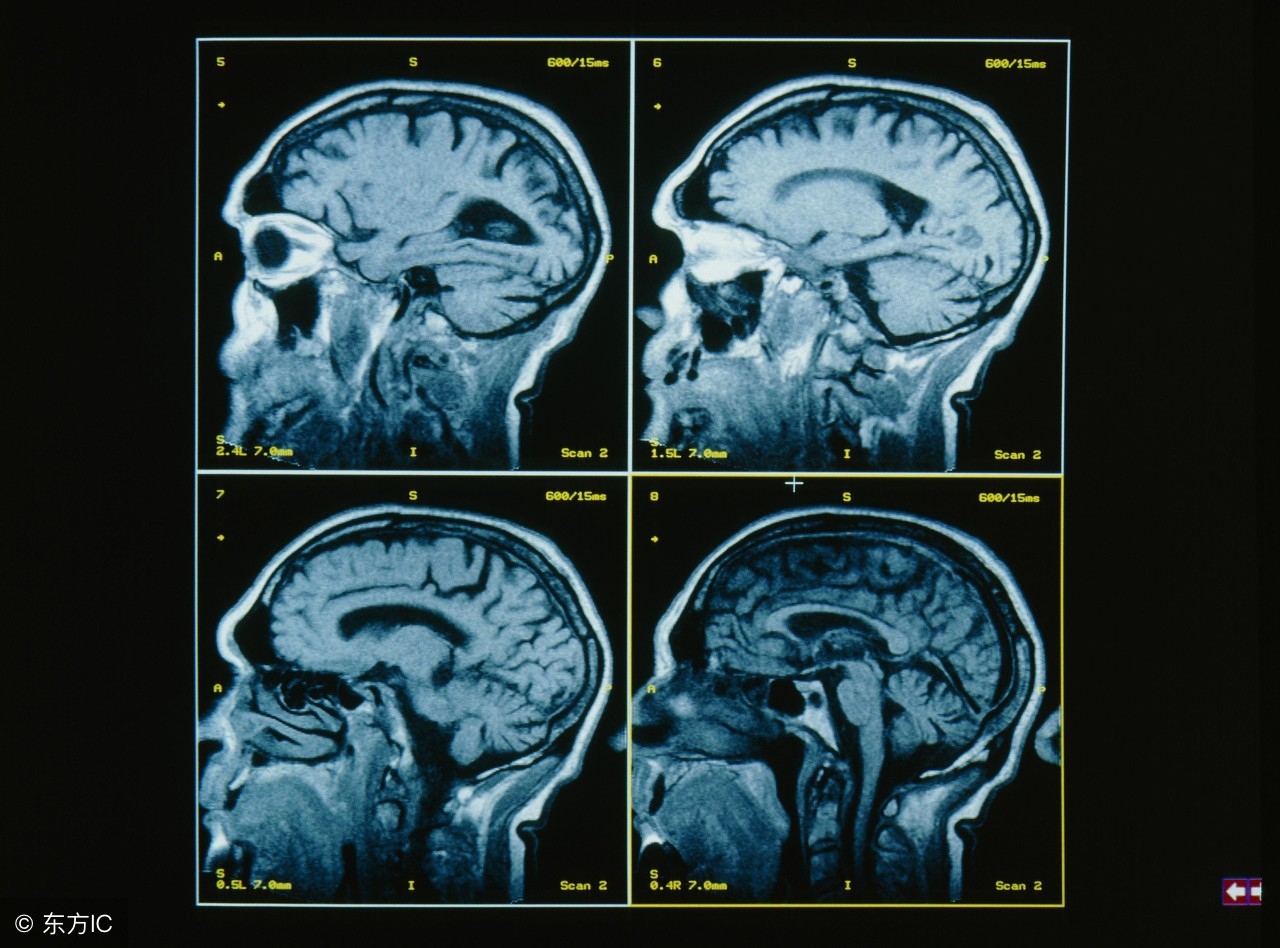

儿童脑瘤易被误诊为感冒,该病的误诊率高达50%。假如孩子头痛、呕吐、视力减退、走路不稳,就很可能是脑部患有肿瘤。而有些医生往往不重视,把它当平常的感冒。有类似症状的孩子要及时到医院做头部CT和MR检查,以免贻误病情。那么,儿童患脑瘤的症状是什么?